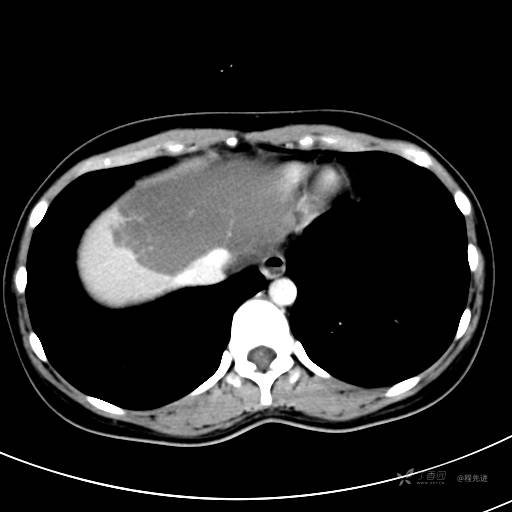

CT平扫+增强,每个序列3张图

CT值 平扫48HU 动脉期66HU 静脉期68HU 延迟期62HU